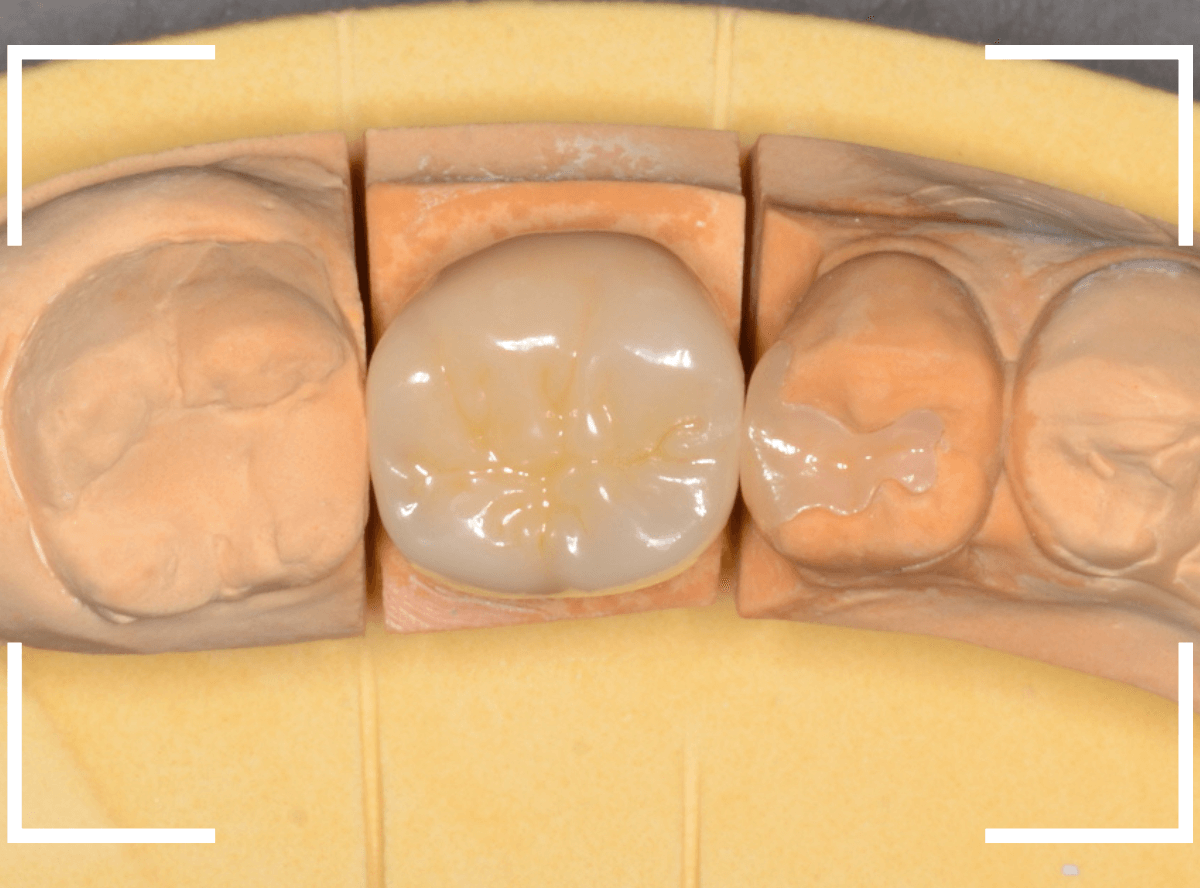

仮歯でしばらく経過観察し、症状がないのを確認した後に、型どりをして(オール)ジルコニア・クラウンを製作しました。

お口の中でジルコニアに置き換えた後も、特に症状なく経過されているようで、ホッとしました。